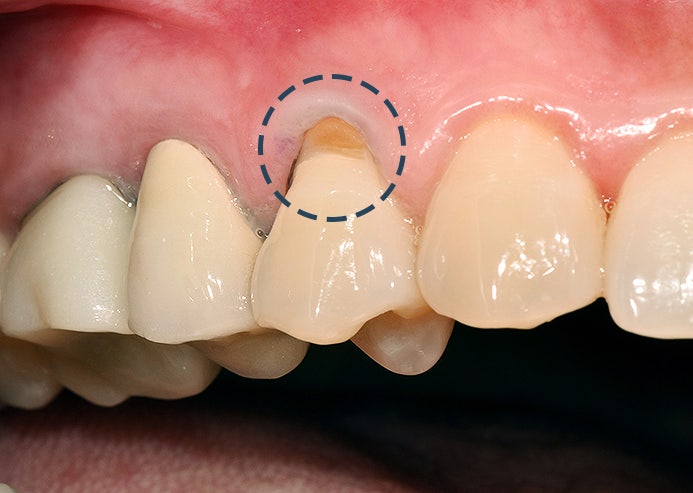

치석은 치아 표면에만 가능하기 때문에 잇몸과 치아 사이에도 생길 수 있습니다. 이때 스케일링을 통해 치석이 제거되면 치아 뿌리가 외부로 노출되지만 코트를 입고 벗을 때 나타나는 외로움처럼 일시적으로 이가 시리게 느껴질 수 있습니다. 이런 증상들은 잇몸이 다시 올라가기 전까지 나타난다고 볼 수 있고 치태의 양이 많거나 스케일링을 정기적으로 받지 않은 분들이라면 증상이 더 심해질 수 있습니다.대부분의 경우 시간이 지나면 사라지게 되는데 잇몸에 염증이 있는 분이라면 더 오랜 시간 증상이 나타날 수 있고, 3주 정도 지나도 지속된다면 치과의원에 내원하여 잇몸 상태를 확인해야 합니다. 출혈은 왜 발생하나요?